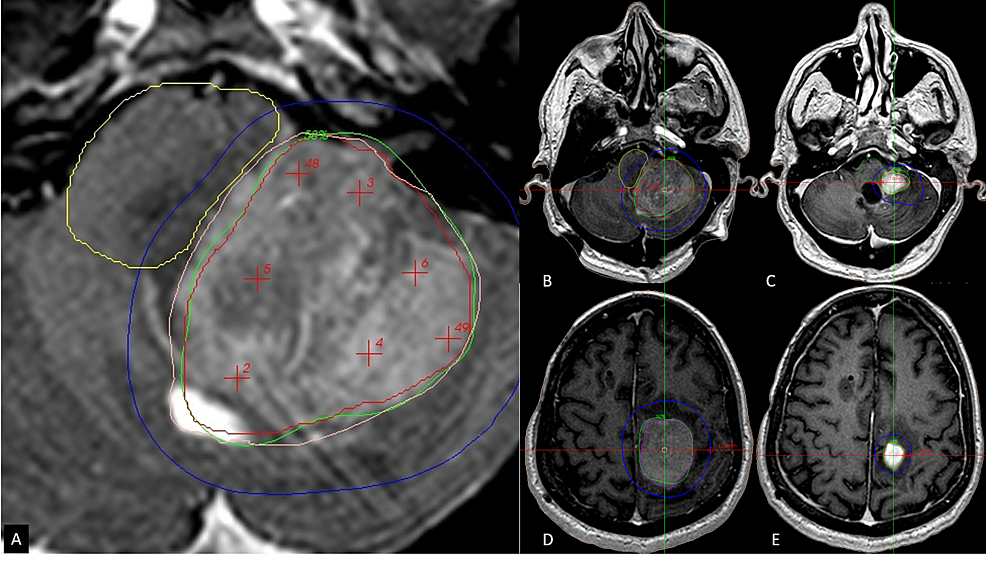

Cureus TwoSession Radiosurgery for Large Primary Tumors Affecting Radiosurgery Brain Lesions Two patient cases were identified to use as the foundation for a discussion of a wide and representative range of management principles: Radiosurgery can be used to treat brain cancers and benign brain tumors. Stereotactic radiosurgery is a very precise form of therapeutic radiation that can be used to treat abnormalities in the brain and spine, including cancer, epilepsy, trigeminal. Radiosurgery Brain Lesions.

Cureus TwoSession Radiosurgery for Large Primary Tumors Affecting Radiosurgery Brain Lesions Stereotactic radiosurgery targets brain abnormalities or the area of your brain that shows symptoms. (a) srs alone for 5 to 15 lesions and. Find out whether you might be a good candidate for this alternative to. Stereotactic radiosurgery is a very precise form of therapeutic radiation that can be used to treat abnormalities in the brain and spine, including cancer,. Radiosurgery Brain Lesions.